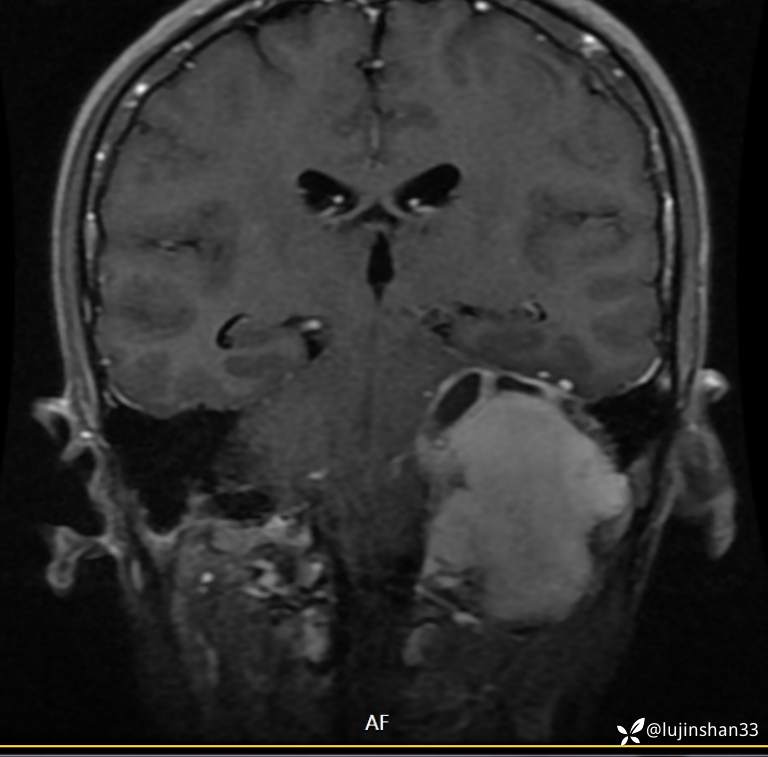

首次术前MRI